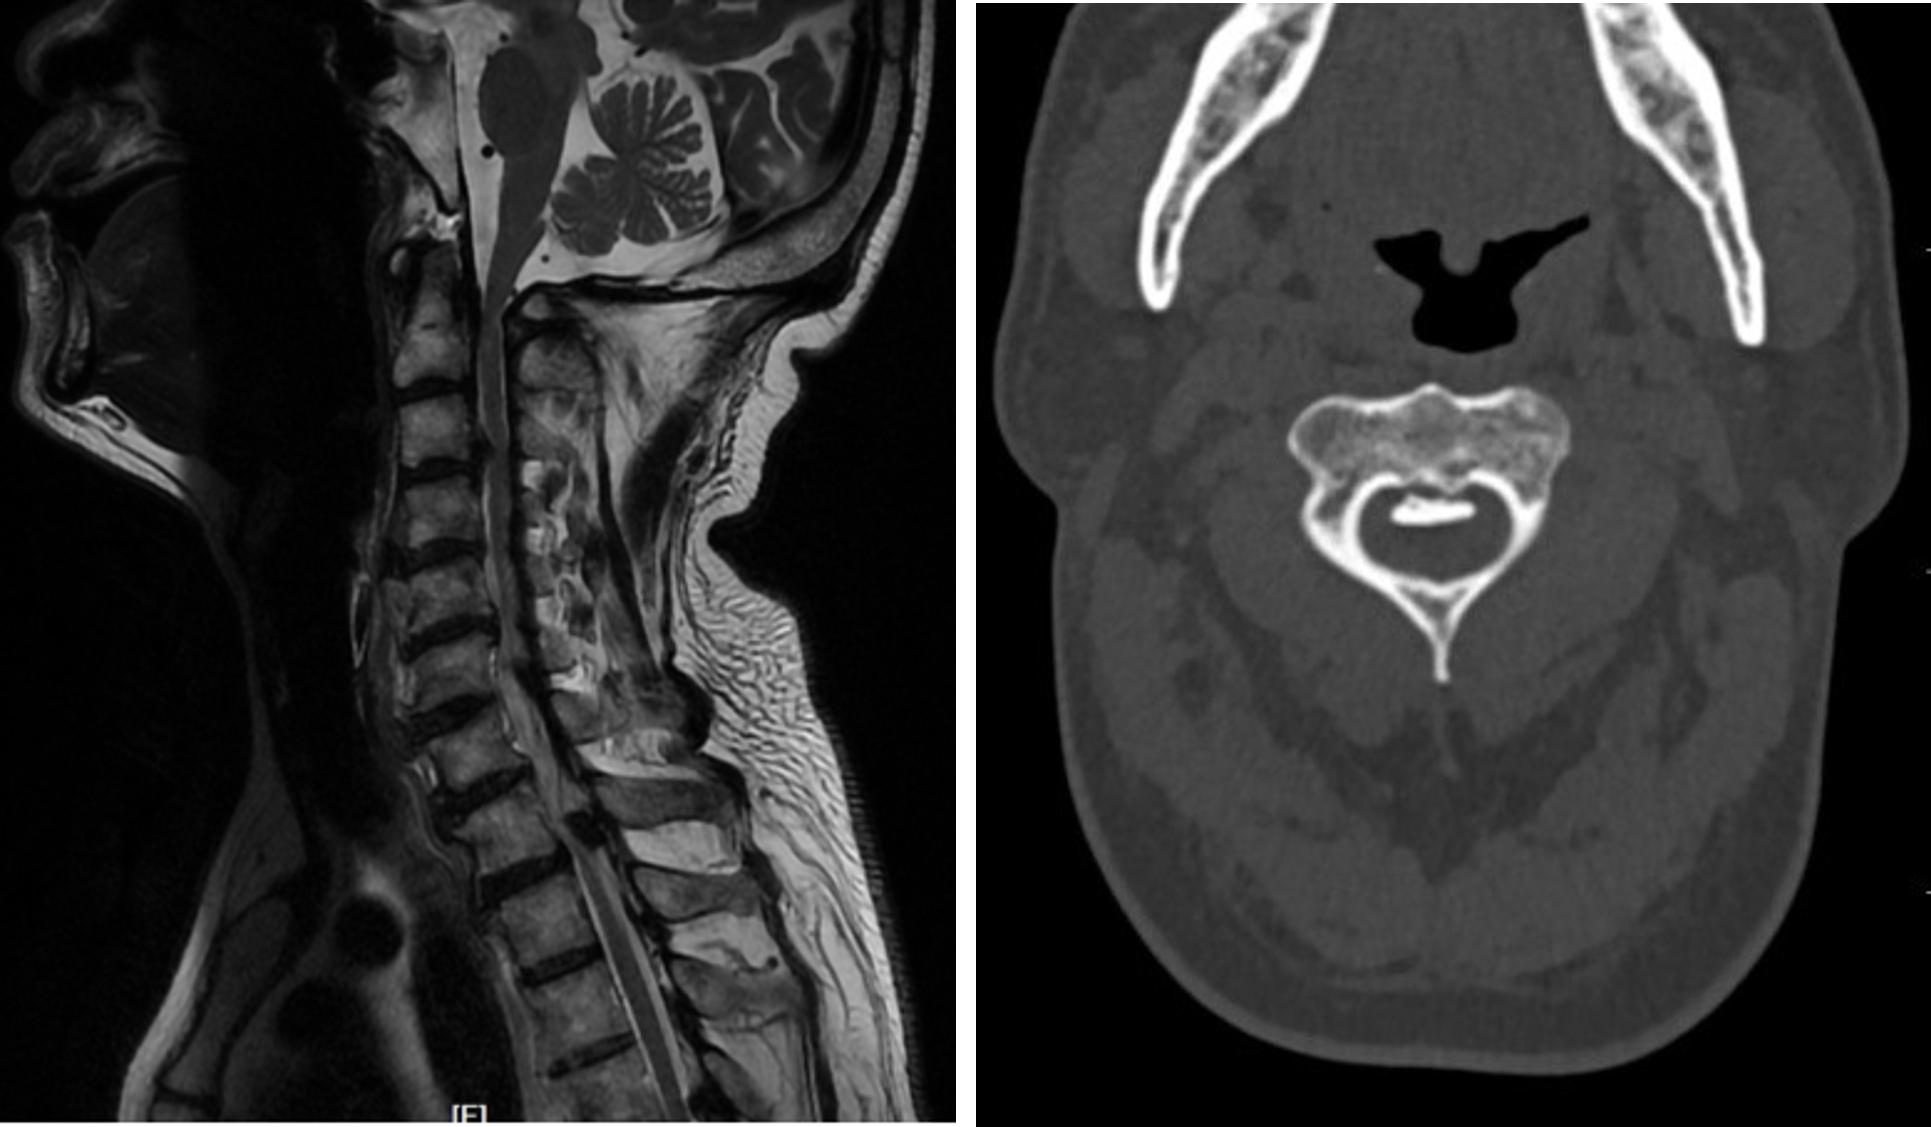

家住镇江的王先生近年来感觉自己的身体出了点问题,一开始是左脚小脚趾有点麻木,后来情况加剧,左手左脚都出现麻木的感觉,走起路来感觉像踩着棉花,这严重影响了他的生活。到当地医院一查颈椎磁共振,提示颈髓严重受压,在他的CT上看到压迫神经的主要是异常增生的骨赘(后纵韧带骨化)压迫了第1~6(下称C1~6)颈髓(第1~2颈椎由于解剖结构特别复杂,在医学上称为上颈椎)。上颈椎压迫脊髓可引起四肢麻木无力、呼吸循环功能障碍等,严重者甚至危及生命。王先生这种情况非常危险,颈髓已严重受压,就好像脖子上背了一个小炸弹,一旦他不小心摔跤,就很有可能危及生命。

王先生本就担心颈椎手术的风险,现在还涉及到上颈椎,风险更大,而不手术自己的颈椎病又将像定时炸弹一样,一直处于危险之中。就在王先生全家一筹莫展之际,听闻苏州有一位姜医生医术精湛,已帮助了许多患者解决了颈椎疾病,于是他们从家乡驱车百里,前往骨科姜为民主任的门诊就诊。姜为民主任在仔细研读过影像资料后,结合王先生的症状体征,当即决定出手为他解决病痛。入院经详细检查后发现王先生同时还患有胸椎管狭窄的问题,但当务之急是治疗高位长节段颈椎后纵韧带骨化症。

而王先生后纵韧带骨化症从C1持续到C6,如何处理C1~2水平的压迫是个难点。由于C1~2解剖上的特点,对这一区域进行手术面临几大难题:一是周围有椎动脉走行,且椎动脉就在手术区域内,稍有不慎就可损伤椎动脉导致难以控制的出血。二是第一及第二颈椎解剖机构特殊,手术易损伤颈髓,会导致掌管呼吸的肌肉瘫痪,危及生命。